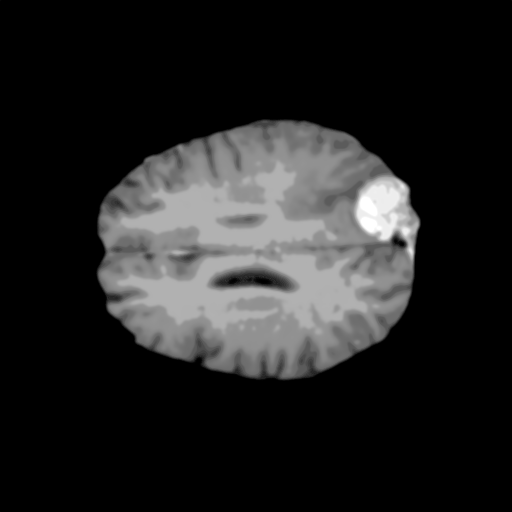

Extensive experiments have been performed in the current setup, and experimental outcomes are reported with the demonstration of numerical and statistical analyses using the proposed QFS-Net, QIS-Net [39], convolutional U-Net [18] and Residual U-Net (URes-Net) architectures [20]. The human expert segmented skull-tripped contrast enhanced DSC brain MR input image slices of size and ROIs are provided in Figure 5 as samples. The demonstration of QFS-Net segmented images followed by the essential post-processed outcome on the slice no. for class level with four distinct activation schemes () are shown in Figure 6. It is evident from the experimental data provided in Table LABEL:tab1 that the proposed QFS-Net performs optimally for the -connected quantum fuzzy pixel information heterogeneity assisted activation () with and gray scale set in comparison with other thresholding schemes and gray scale sets under the four evaluation parameters () [44]. The segmented tumors obtained using the proposed self-supervised procedure under class transition levels with four different thresholding schemes , , and are demonstrated in Figures 7- 8 for the class boundary sets and [39], respectively. The segmented images using the remaining two class boundary sets ( and ) [39] are provided in the supplementary materials section. The segmented ROIs describing the whole tumor region after the masking procedure using QIS-Net, U-Net and URes-Net are also reported in Figure 9.